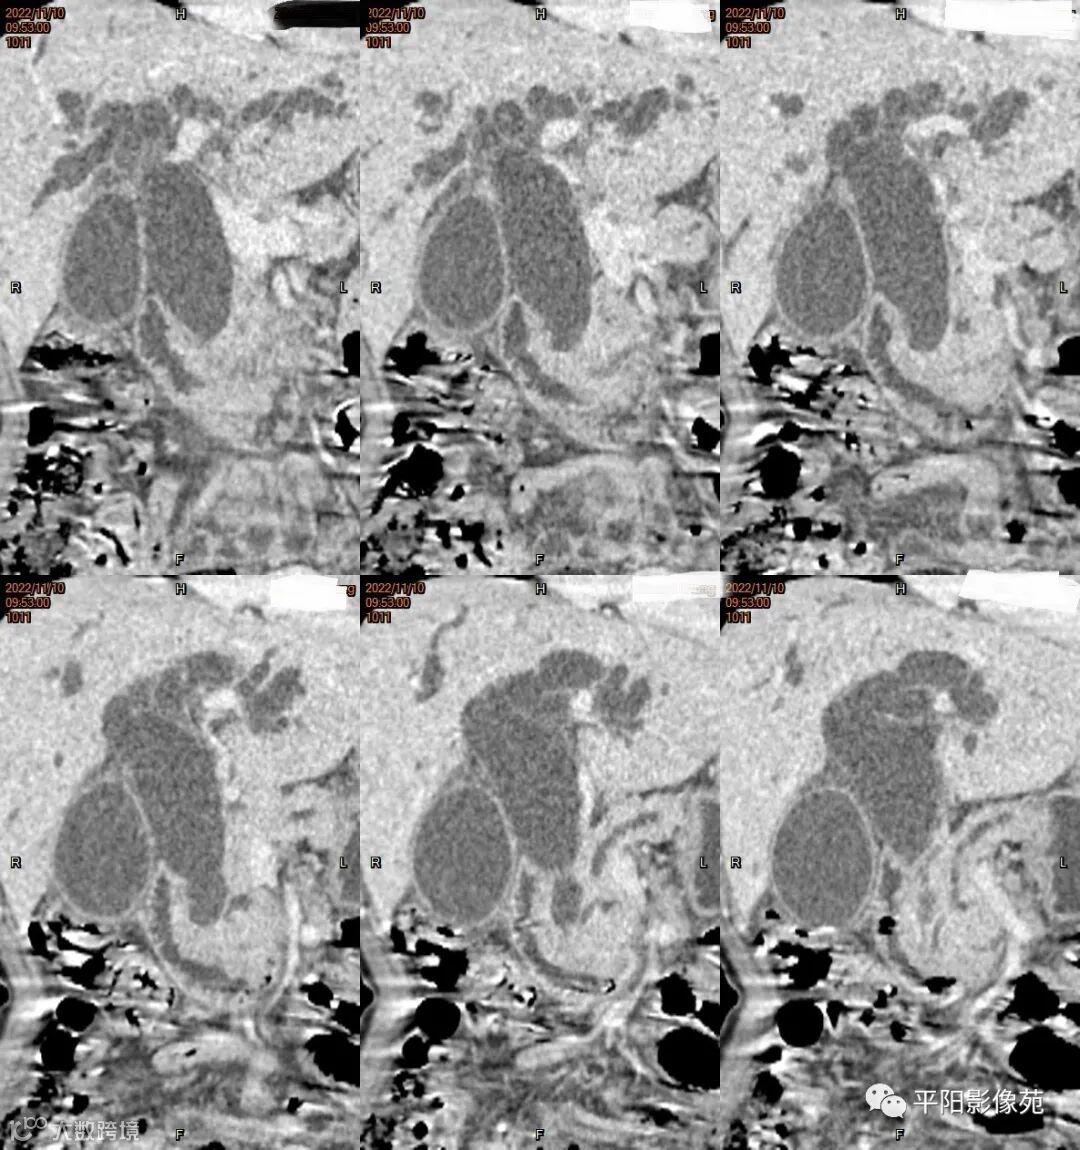

影像学检查

CT

影像表现: